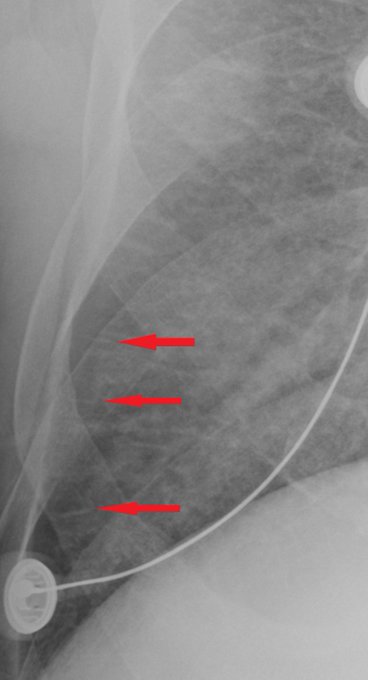

Developement of Kerley B lines. First CXR=normal, 2nd CXR=mild edema w/ Kerley B lines, 3rd image, coned view of right lateral chest, red arrows show Kerley lines. https://t.co/5vyES9rKOs